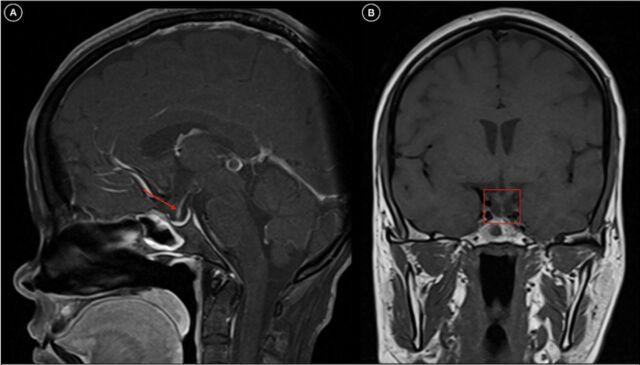

Sheehan syndrome is the infarction of a pituitary gland that has been physiologically enlarged as a result of postpartum bleeding. Agalactorrhea and amenorrhea are classic symptoms, but a constellation of manifestations occurs in both the acute and chronic forms. These manifestations can remain largely nonemergent unless Sheehan syndrome is complicated by severe adrenal dysfunction secondary to an inciting event such as dengue. We present a case of Sheehan syndrome that was uncovered in a patient with a dengue infection presenting as adrenal crisis. A 45-year-old female presented with symptoms of acute gastroenteritis and severe dehydration. Her medical history was significant for secondary amenorrhea for 14 years after her last delivery followed by symptoms of endocrine dysfunction. At presentation, the patient was in adrenal crisis with hypotension, hypoglycemia, and hyperthermia. Dengue nonstructural protein 1 antigen was positive, along with signs of plasma leakage. Bloodwork showed bicytopenia with abnormal liver enzymes. Ultrasonography and computed tomography of the abdomen were suggestive of serositis with acalculous cholecystitis. Magnetic resonance imaging of the brain revealed an empty sella. Anterior pituitary hormone levels were significantly decreased with low serum cortisol, and the patient's thyroid profile analysis suggested secondary hypothyroidism. The final diagnosis was Sheehan syndrome presenting as adrenal crisis precipitated by severe dengue fever. The patient was managed conservatively and discharged on hormone supplement therapy. Sheehan syndrome is an important cause of panhypopituitarism in the developing world. Knowledge of Sheehan syndrome is important to help prevent its occurrence and reduce its resultant multifactorial effects.

席汉综合征是由于产后出血导致生理性增大的垂体发生梗死。无乳和闭经是典型症状,但急性和慢性形式均会出现一系列表现。这些表现大多不会很紧急,除非席汉综合征因登革热等诱发事件并发严重肾上腺功能不全。我们报告一例在因登革热感染表现为肾上腺危象的患者中发现的席汉综合征病例。一名45岁女性出现急性胃肠炎和严重脱水症状。她的病史显示,末次分娩后继发闭经14年,随后出现内分泌功能障碍症状。就诊时,患者处于肾上腺危象状态,伴有低血压、低血糖和高热。登革热非结构蛋白1抗原呈阳性,伴有血浆渗漏迹象。血液检查显示全血细胞减少伴肝酶异常。腹部超声和计算机断层扫描提示浆膜炎伴无结石性胆囊炎。脑部磁共振成像显示空蝶鞍。垂体前叶激素水平显著降低,血清皮质醇水平低,患者的甲状腺功能分析提示继发性甲状腺功能减退。最终诊断为席汉综合征,表现为严重登革热引发的肾上腺危象。患者接受保守治疗,出院时接受激素补充治疗。席汉综合征是发展中国家全垂体功能减退的重要原因。了解席汉综合征对于预防其发生和减少其产生的多因素影响很重要。